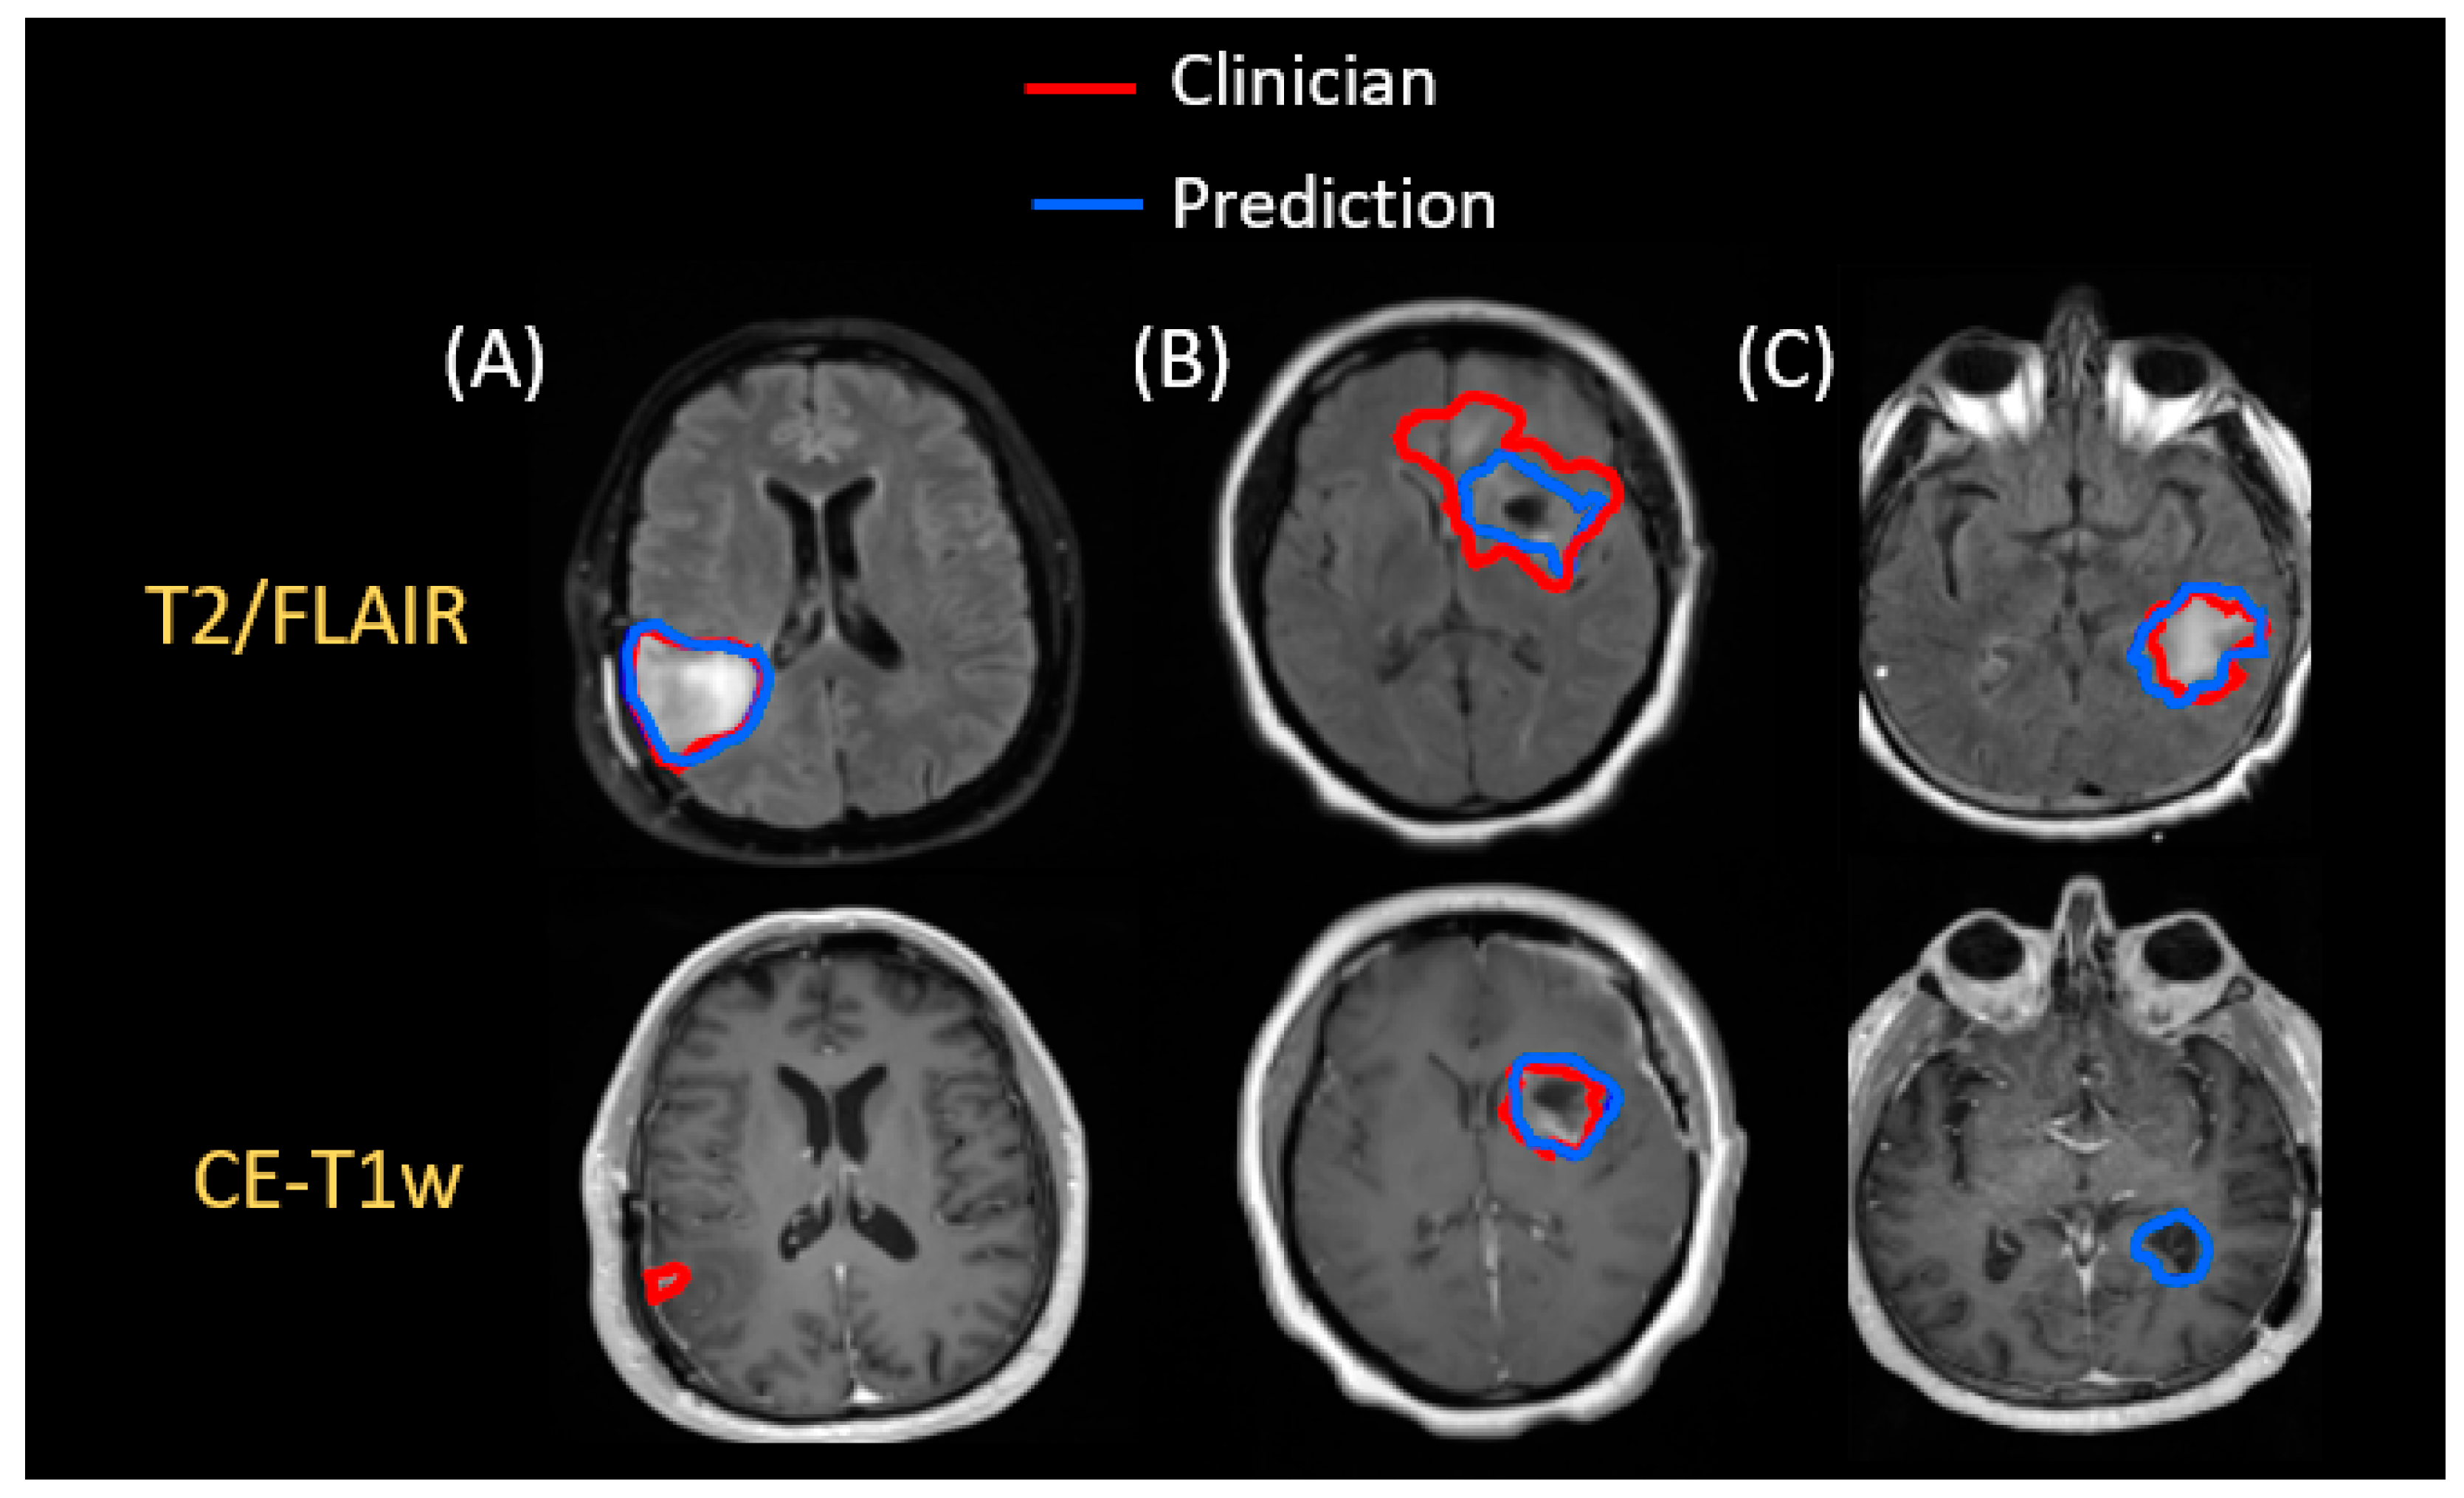

3.1. Segmentation for RT Planning

3.2. Application of Segmentation in Longitudinal Tracking